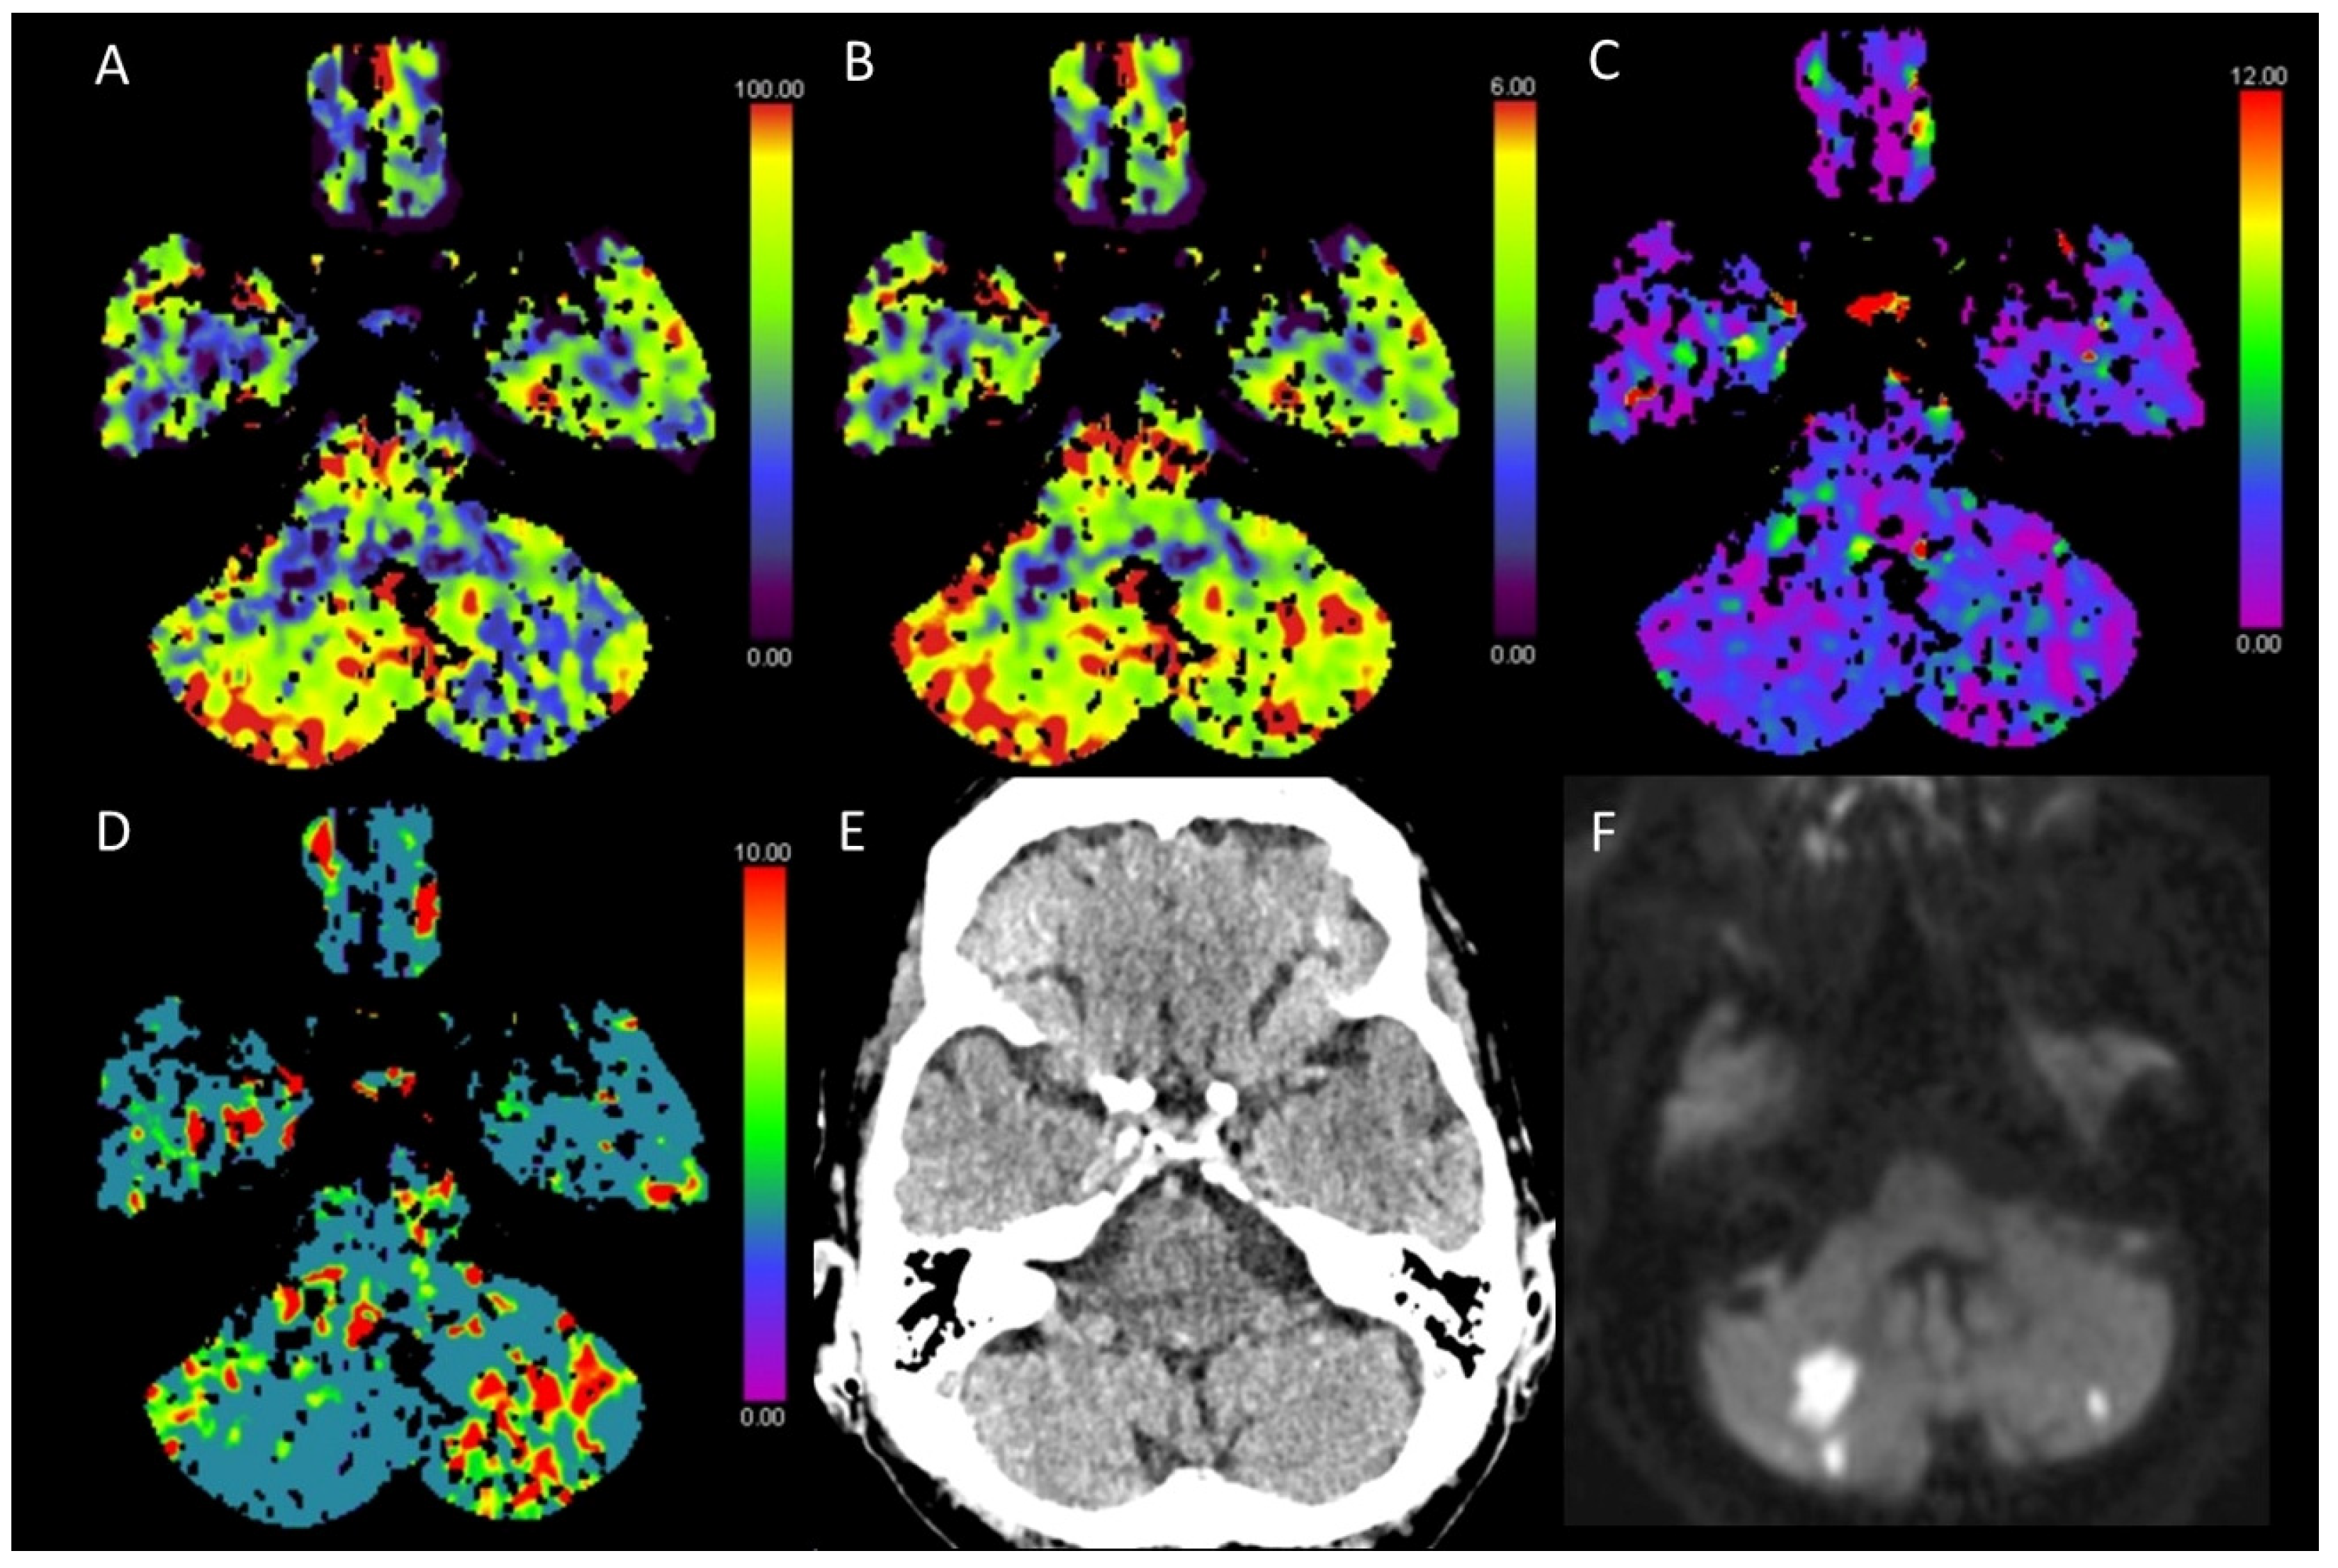

3.2. Acute Posterior Fossa Infarcts

3.3. Global Hypoxic-Ischemic Injury/Brain Death